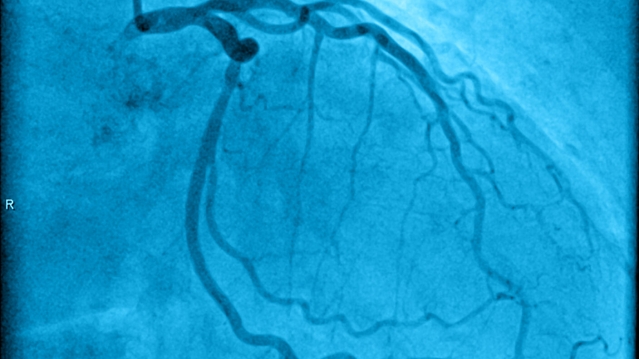

Study groups Coronavirus (SARS-CoV-2) Critical Care Gastroenterology Cardiology Neurology Endocrinology Dentistry and oral surgery Phytotherapy Microbiology Angiology Otology